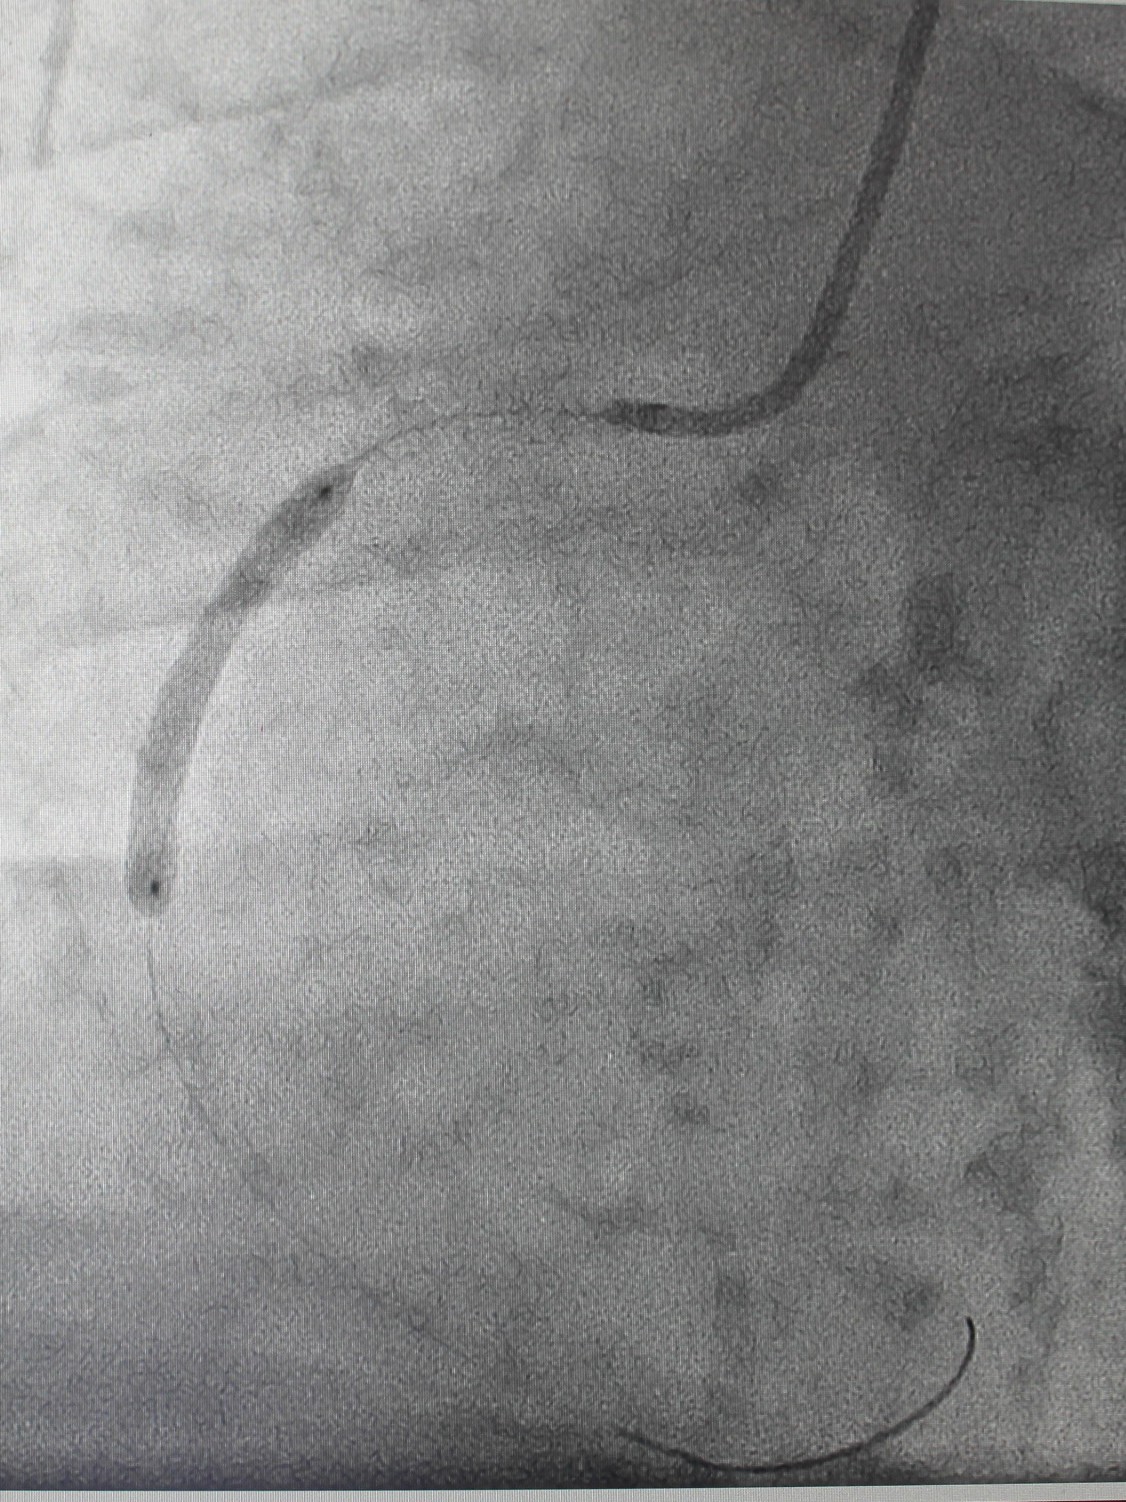

По экстренным показаниям проведена коронароангиография, выявлено стенозирующее многососудистое поражение: стеноз (сужение) передней межжелудочковой ветви левой коронарной артерии 80% в проксимальной трети, стеноз огибающей ветви 75% в дистальной трети (при том, что существенным рассматривают сужение артерии > 50%), тромботическая окклюзия правой коронарной артерии (в проксимальной трети). Рентгенхирурги выполнили тромбэкстракцию из правой коронарной артерии, баллонную ангиопластику со стентированием правой коронарной артерии (2 стента с лекарственным покрытием). Операция продолжалась около часа, после чего пациент продолжил лечение под наблюдением врачей отделения кардиореанимации; через двое суток был переведен в отделение кардиологии для дальнейшего лечения.

| Обнаружены участки стенозирования артерии | Установлены 2 стента, стенты раскрыты | На контрольной ангиограмме: коронарный кровоток восстановлен, раскрытие стентов полное, позиционирование адекватное |